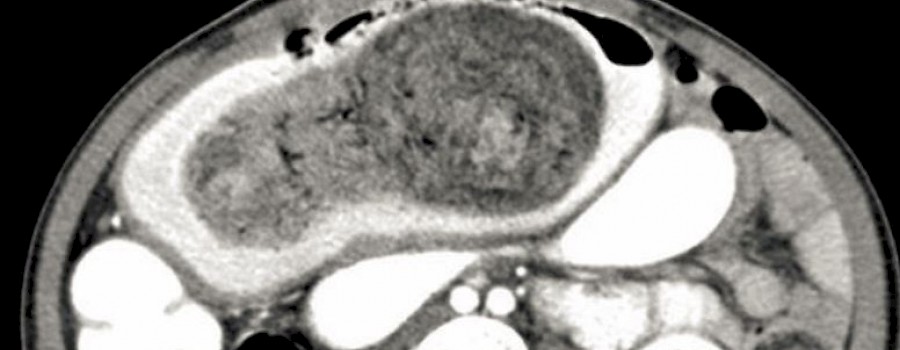

Das im Volksmund bekannte Rapunzel-Syndrom (Trichophagie) beschreibt ein zwanghaftes Verhalten des Patienten. Es beinhaltet das Verschlucken sowie das Essen der eigenen Haare über einen längeren Zeitraum.